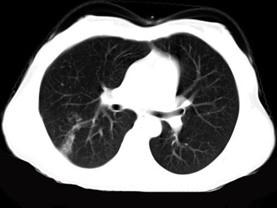

问题 女,40岁,间断咯血一周,低热,行胸部CT扫描如图,选择最可能的诊断为 ( )

选项 A、支气管囊肿并感染 B、肺脓肿 C、肺部感染 D、支气管扩张并感染 E、肺结核

答案 E